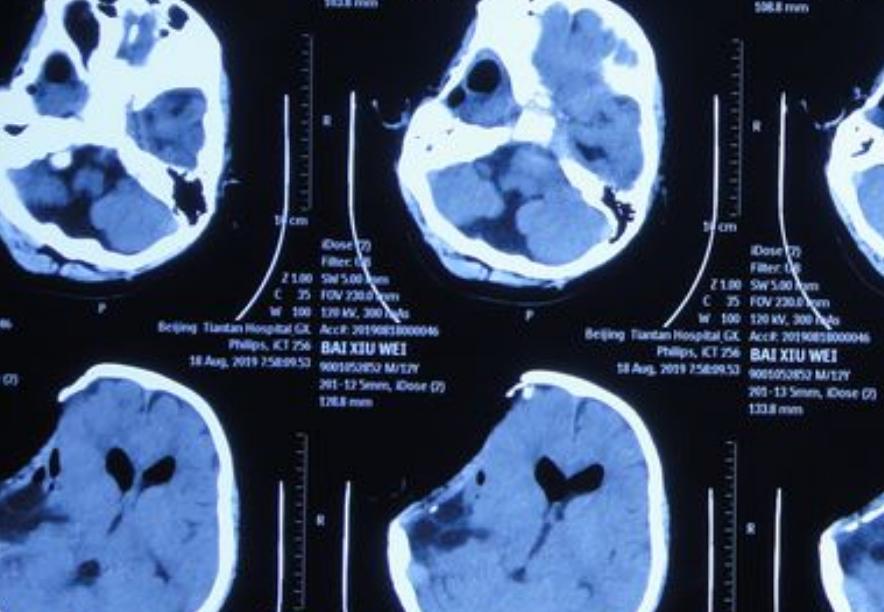

万一是耳朵内部长了肿瘤,一定要去医院做专业的CT检查。肿瘤的大小直接决定了疾病的程度。如果是恶性的那么可能是癌症,需要及早接受治疗。此外真菌性的耳道感染是很难清洗干净的,所以必须要由专业的医生来进行处理。

耳内镜检查主要是对外耳道和鼓膜形态进行检查,它通过显示器和照相打印的方式记录鼓膜变化,从而直接观察到内管有无炎症或其他功能退行性改变。比如耳内管是否通畅。而颞骨CT检查可以明确耳朵具体病变情况。通过检查会发现耳半硅管的畸形、内淋巴囊和外淋巴囊是否存在发育畸形的问题。